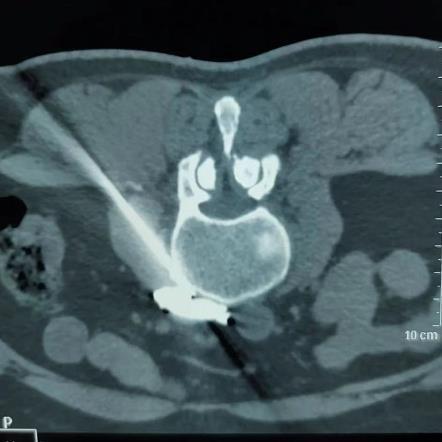

腰交感射频术是在超声引导下将0.7mm(绣花针那么细)的射频针达L2和L4椎体前外侧的交感神经节处,达到目标靶点后,再借助CT\X线做最后定位。

超声引导结合影像定位是疼痛科的特色技术。超声具有可视化、实时动态观察、准确率高、无辐射等优点,就像精确制导导弹一样,同时又可避免对靶目标周围血管、神经的损伤,从而达到理想的治疗效果。